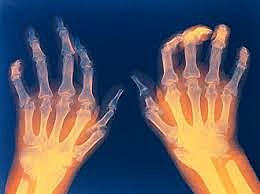

• Rheumatoid arthritis pathway

Rheumatoid arthritis pathway

People find a pathway linked to cartilage deterioration and bone attrition of rheumatoid arthritis.